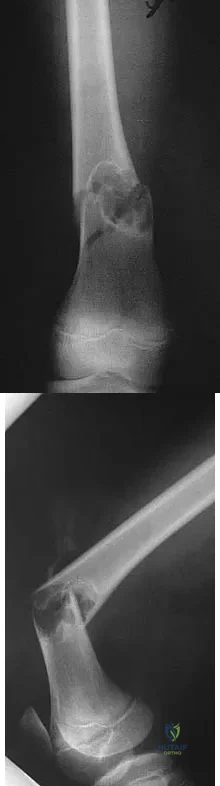

Question 16

A 5-year-old boy sustained an elbow injury. Examination in the emergency department reveals that he is unable to flex the interphalangeal joint of his thumb and the distal interphalangeal joint of his index finger. The radial pulse is palpable at the wrist, and sensation is normal throughout the hand. Radiographs are shown in Figures 6a and 6b. In addition to reduction and pinning of the fracture, initial treatment should include

Explanation